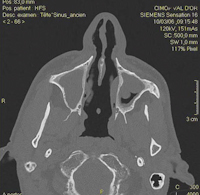

Perforation de cloison après utilisation de cocaïne